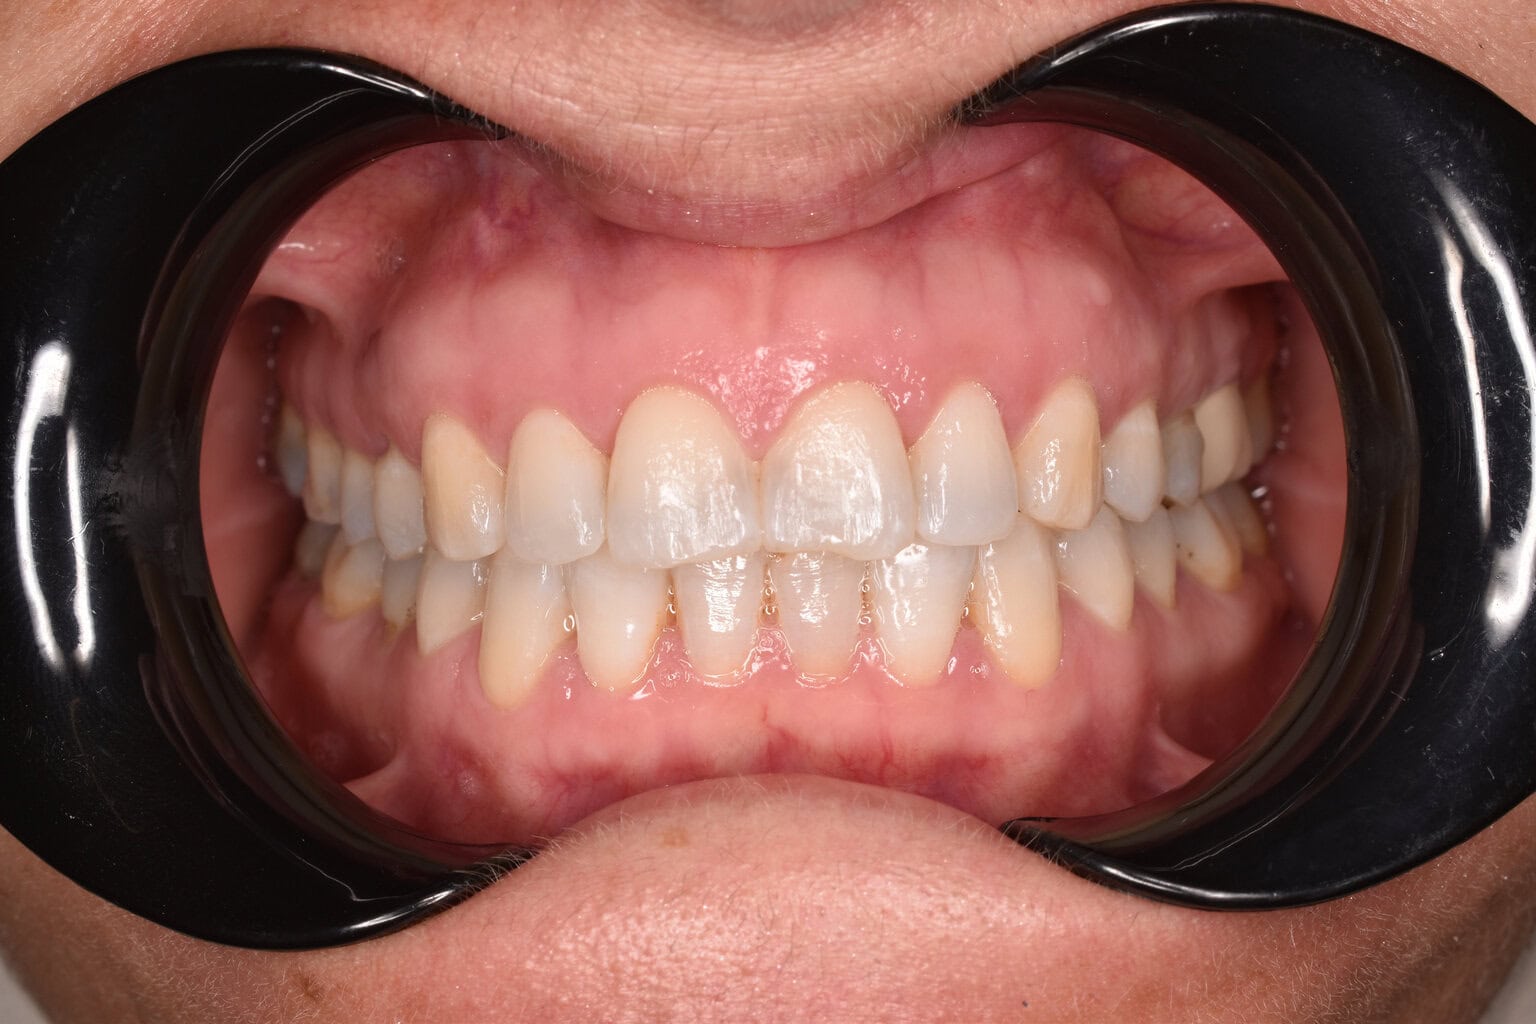

Vorher-Nachher-Ergebnisse

Echte Ergebnisse. Echte Menschen.

Jede Behandlung bei TIEFBLAU Kieferorthopädie ist so individuell wie der Mensch dahinter. In unserer Vorher-Nachher-Galerie zeigen wir Ihnen echte Behandlungsergebnisse aus unserer Praxis in der Kölner Südstadt: Schonend erzielt, präzise geplant und mit dem Anspruch, den wir seit über 40 Jahren an jede Behandlung stellen.

Die Bilder geben Ihnen einen Eindruck davon, was moderne Kieferorthopädie leisten kann, ob bei Kindern, Jugendlichen oder Erwachsenen.

Der sichtbare Unterschied

Dokumentiert. Überzeugend. Nachhaltig.